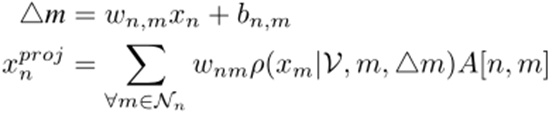

其中Nn相邻体素n。朴素方法通常采用具有冗余连接和交互节点间参数的全连通图,很难进行优化。更重要的是,线性组合方法缺乏自适应采样的能力,因为不同的图像包含不同的脑胶质瘤上下文信息(如位置、大小和形状)。作者采用自适应采样策略来解决这个问题:

其中wnm∈R3×(K×C)和bnm∈R3×1are为每个原始特征Xn通过随机梯度得体单独学习的移位距离。ρ()是一个三线性插值采样器,在已知变形△m和交互图节点V的全部集合的情况下,对特征节点xm周围移位的特征节点进行采样。